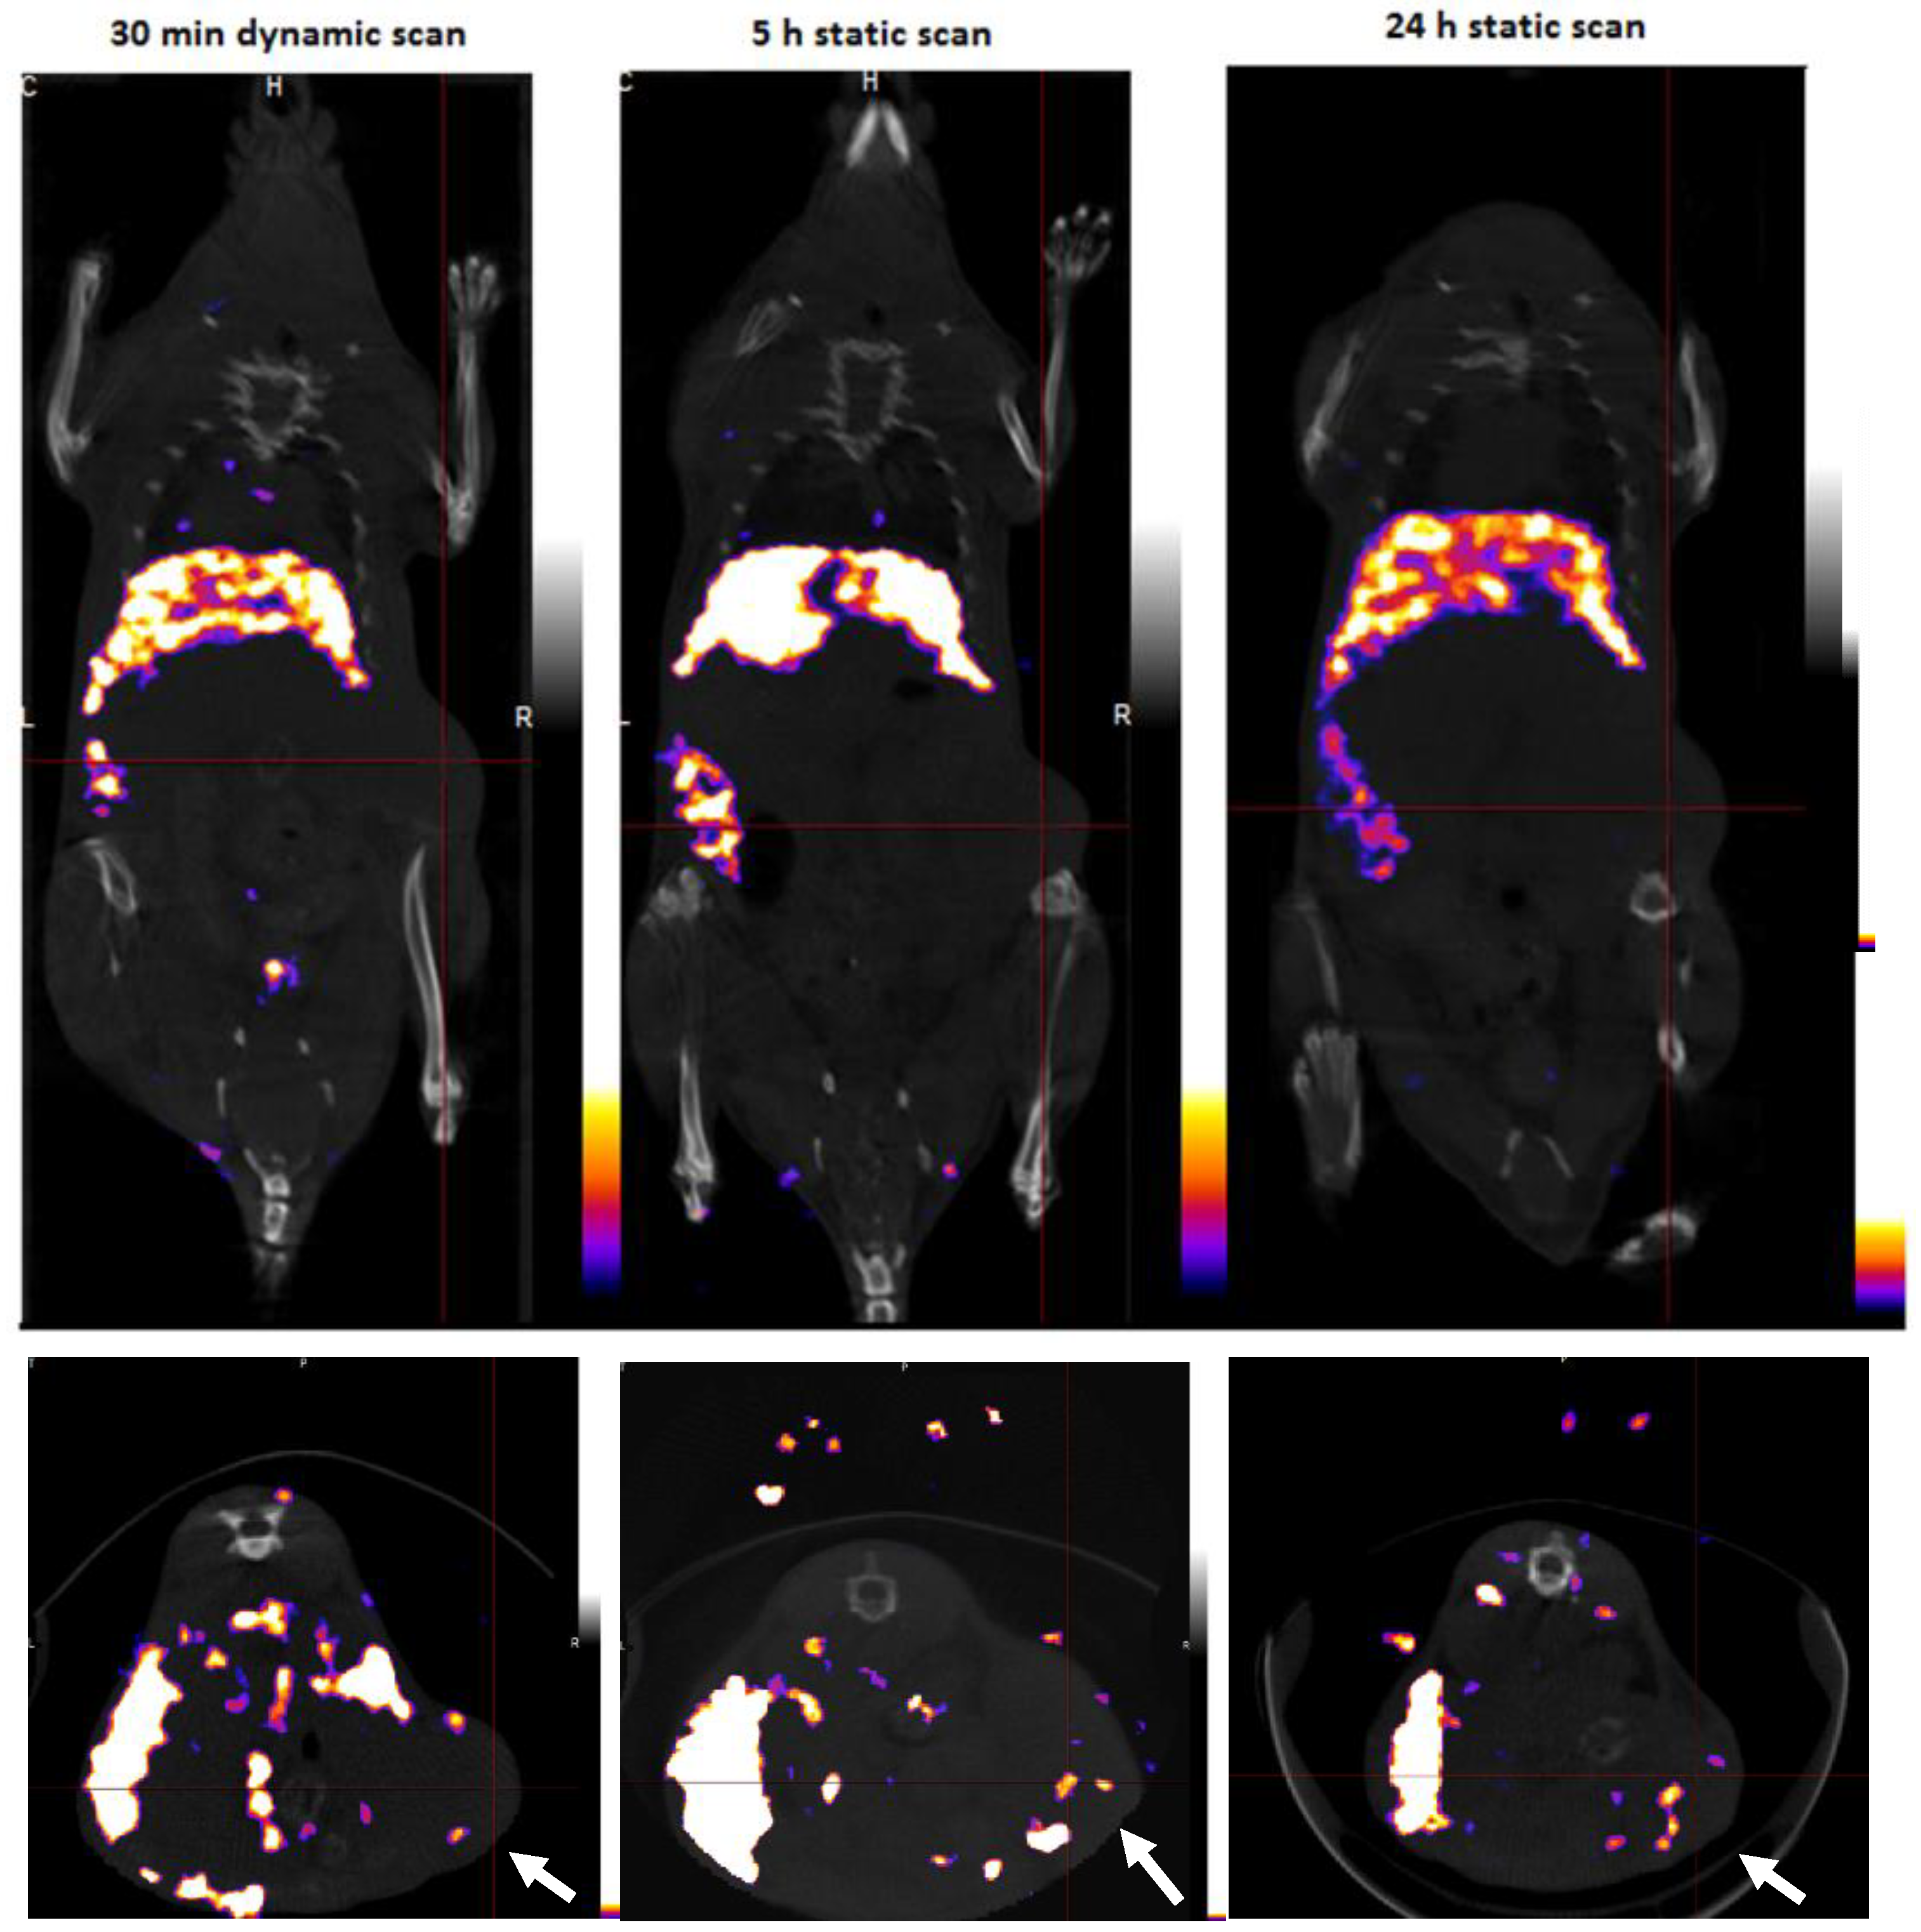

3.4. SPECT/CT Imaging

3.5. Tumor Autoradiography